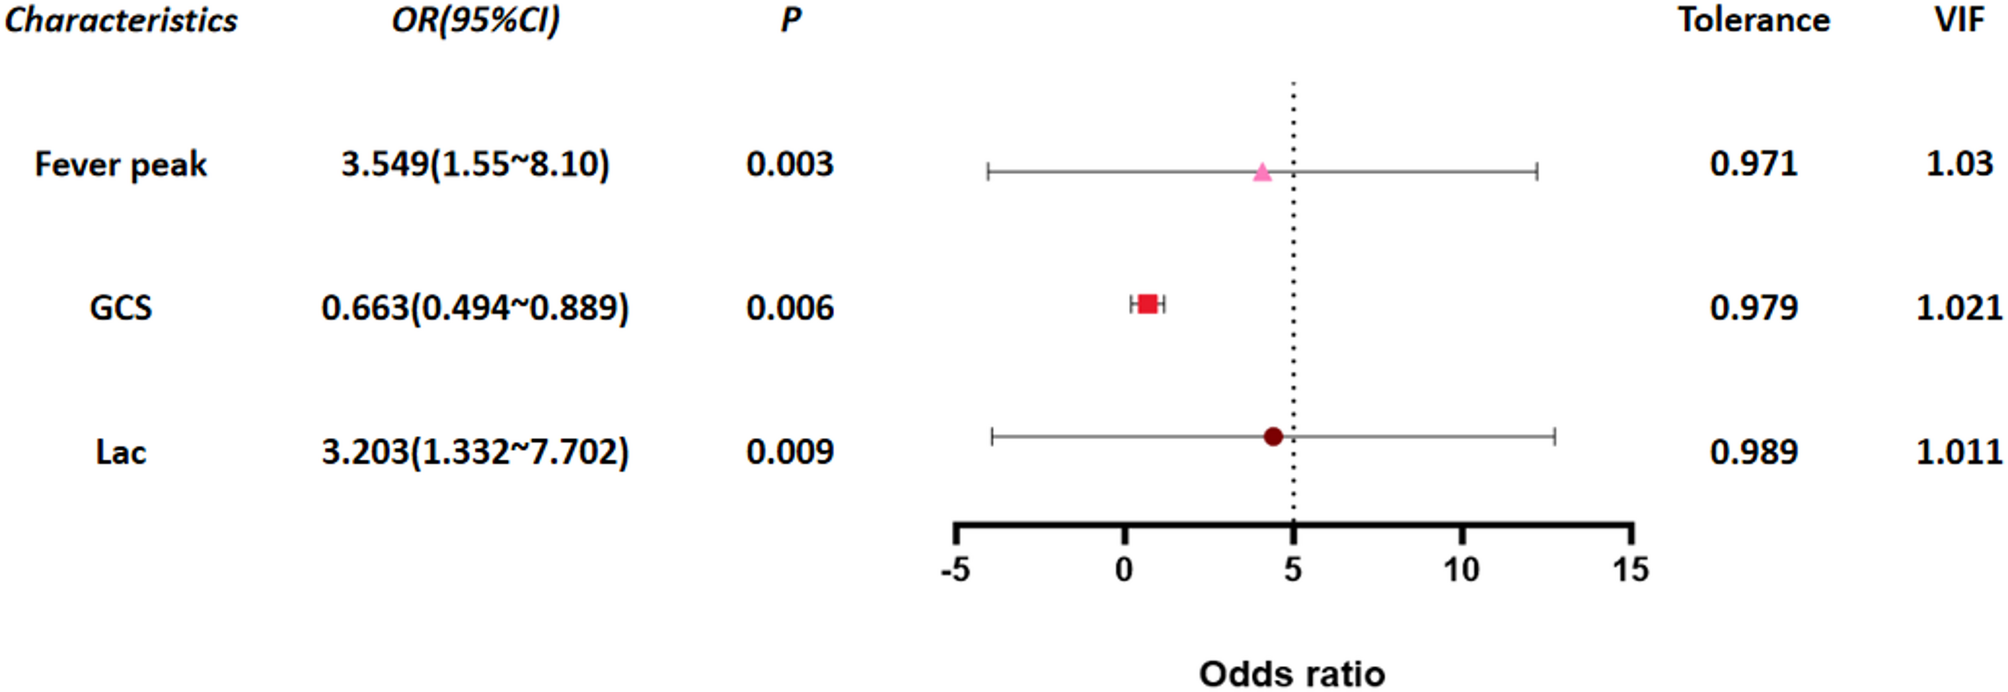

This study is a retrospective case-control study. Data of 6,647 pediatric influenza patients treated at Wuhan Children’s Hospital Affiliated to Tongji Medical College of Huazhong University of Science and Technology from…